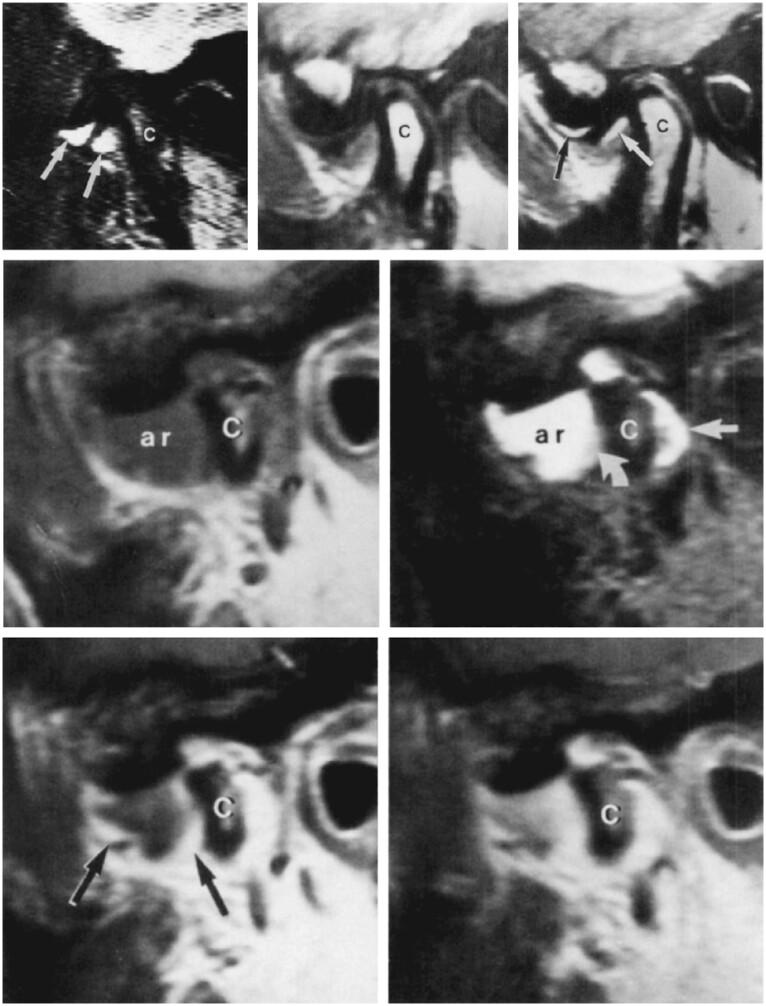

In this pictorial review, an introductory paragraph emphasizes the significance of some anatomical aspects for optimal imaging of the temporomandibular joint (TMJ). The most frequent pathologies: internal derangement (ID) and osteoarthritis (OA) are comprehensively discussed and illustrated. Less common conditions: ID and OA-like changes in children and adolescents, idiopathic condylar resorption, inflammatory arthritis, and juvenile idiopathic arthritis are briefly discussed. A short paragraph on differential diagnostics in young patients is included followed by a brief comment on expansile lesions that occasionally may occur in the TMJ.